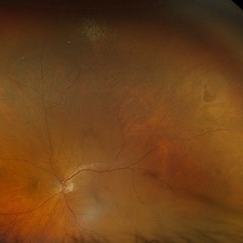

Total Retinal Detachment

Total Retinal Detachment

Aug 6 2025 by Korey Starkey

59 year-old patient presents with total retinal detachment at first visit in OD. Recommending prompt surgical intervention.

Photographer: Korey Starkey

Imaging device: Optos

Condition/keywords: color fundus photograph, Optos, retinal detachment, total retinal detachment